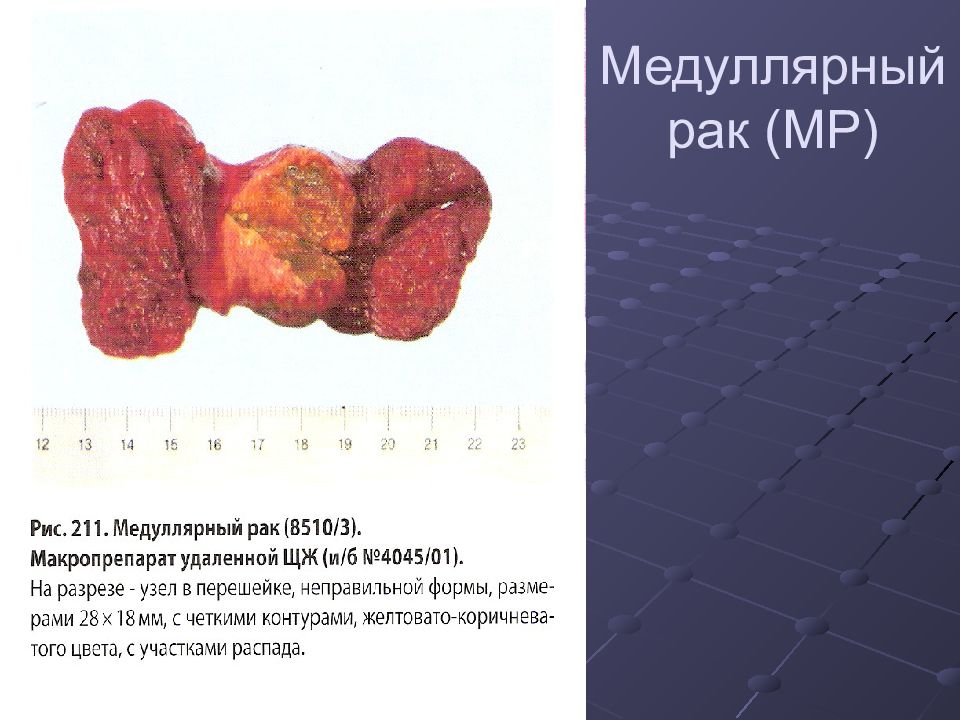

Фотографии опухоли медуллярной аденокарциномы

Раздел: Снимки-откровения